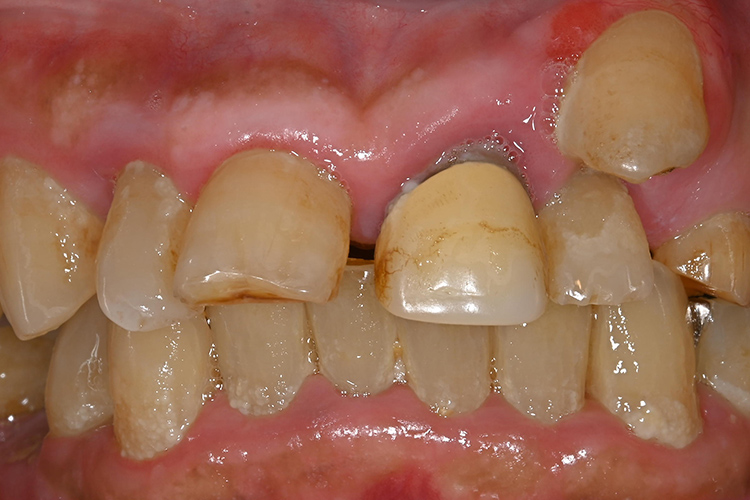

この患者様は、口腔内全体において重度の歯周病が生じており、歯磨き指導、クリーニング、Flap手術等を行ったが、歯周ポケットが深すぎるためブルーラジカル適用症例と診断し、施術を行いました。

実施前

施術前のレントゲンと口腔内写真です。施術前にプラークの除去を行ってから、施術します。